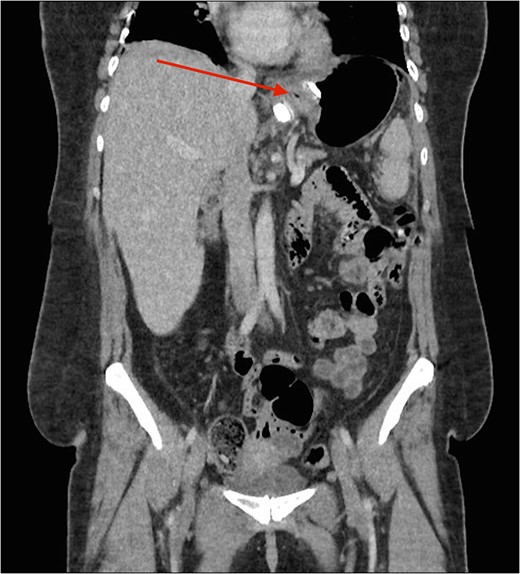

CT image demonstrating the air loculation site next to the band (red arrow).